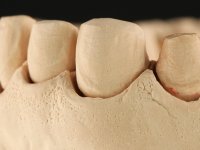

Realizado o diagnóstico e tomada a decisão quanto ao tratamento a executar, tornou-se importante definir qual a sequência de trabalho a adotar no sentido de conseguir a reabilitação da D.V.O. (V.D.O), de forma progressiva e equilibrada. Na primeira fase fez-se uma pré-impressão da arcada inferior com silicone tipo “putty” e em seguida realizou-se o preparo dentário de todo o sector posterior. O preparo para os overlays foi feito coronalmente à linha amelo cementaria no sentido de ser o mais conservador possível. A impressão foi feita com técnica de dupla mistura após afastamento gengival realizado com pasta de caulino. A provisória foi realizada com resina composta de polimerização dual. Em laboratório foram realizados os overlays após se ter aberto ligeiramente (1,5mm) a D.V.O. nos modelos montados em articulador semi-ajustável. Simultaneamente o sector antero-inferior foi encerado no sentido de acompanhar este aumento da D.V.O. Também foi confecionada uma chave de silicone translucido para posterior confeção dos provisórios antero-inferiores. Em boca foi primeiro realizada a provisionalização dos dentes anteriores utilizando resina composta previamente aquecida após preparação das superfícies dentárias para a adesão. Foi colocado o dique de borracha para promover o isolamento absoluto e posteriormente foram colados os overlays. Em laboratório foi realizada nova chave de silicone para confecionar os provisórios antero-superiores. Seguidamente em boca foram preparados os seis dentes antero-superiores após colocação do fio de afastamento gengival. Feita a preparação adequada das superfícies dentárias foi realizada a impressão com técnica de dupla mistura e a respetiva provisória. Em laboratório foram confecionadas 6 facetas feldespáticas num modelo de trabalho tipo “Geller”. A provisória foi removida e as facetas foram coladas em boca utilizando um isolamento relativo competente. Esta opção foi tomada em virtude de uma prévia experiencia negativa com a colocação do dique de borracha na mandibula. Após a colagem dos laminados antero-superiores foram dadas 12 semanas para avaliar a adaptação do paciente à nova situação e então iniciar a confeção das facetas antero-inferiores. Após colocação do fio de afastamento gengival. foram feitos os preparos dentários adequados e em seguida foi feita a impressão. Também foi feita a preparação do dente 3.4 que, entretanto, tinha sofrido uma fratura do overlay. As facetas e a restauração do 3.4 foram realizadas num modelo de trabalho tipo “Geller”. Após remoção da provisória, as facetas foram coladas em boca, utilizando um isolamento relativo pelas razões apontadas anteriormente. Após colocação do trabalho o paciente foi reabilitado por outros colegas com um implante na zona do 2.6 e substituição da coroa aparafusada sobre o implante colocado no local do 3.5. Posteriormente surgiram fraturas nos overlays dos dentes 4.7 e 3.7 que foram reabilitados com overlays em Zr.